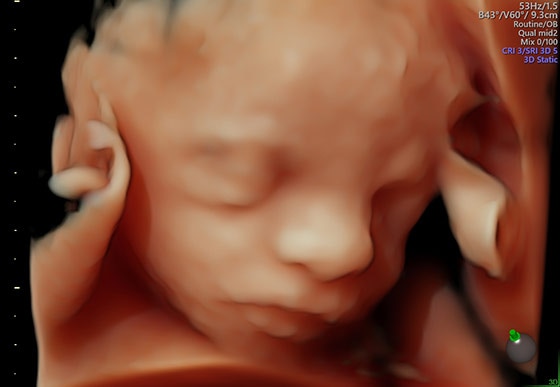

- Лёгкое получение 3D/4D-изображений дает вам дополнительную диагностическую информацию и облегчает взаимопонимание с пациентами

- HDlive – технология объемной визуализации, позволяющая получать удивительно реалистичные изображения.

Новое представление структур с беспрецедентной глубиной и анатомической чёткостью с помощью технологии HDlive — важнейшего инструмента решения проблем.